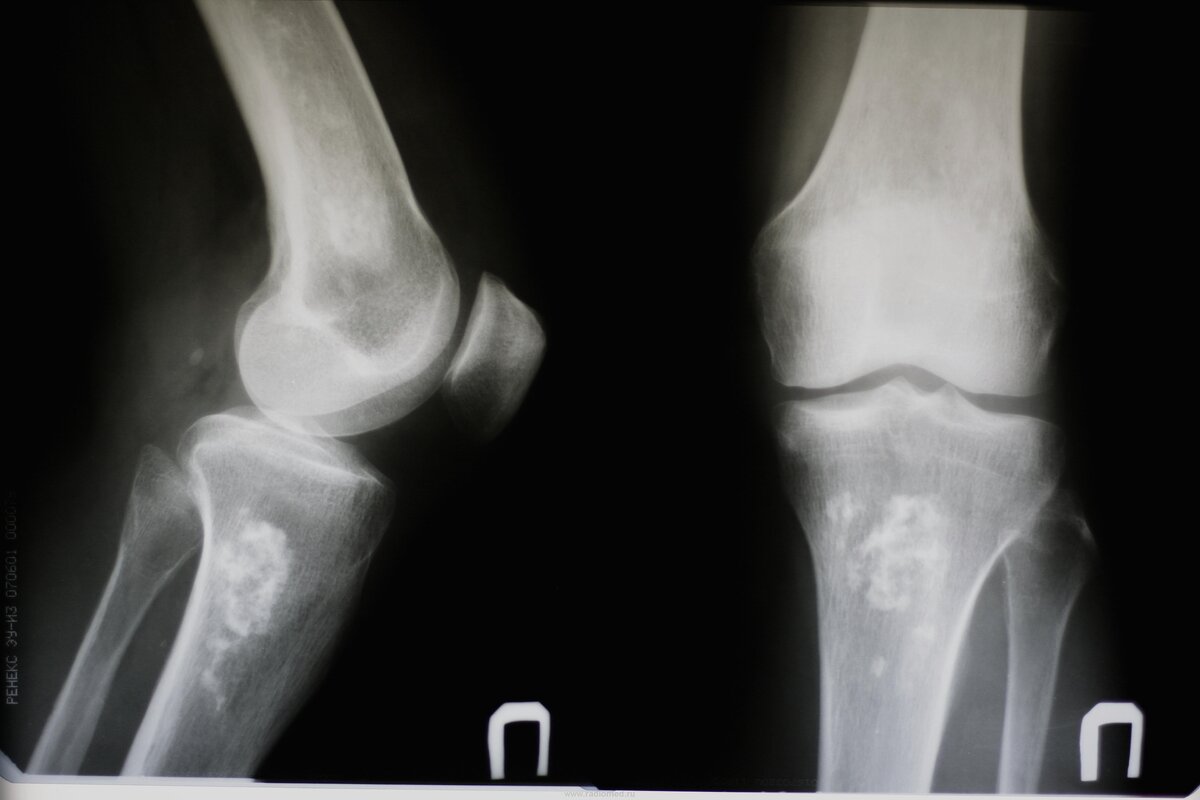

Самый банальный и, пожалуй, один из самых неэффективных пунктов. Но его лучше выполнить, чтобы исключить какие-то серьезные травмы и патологии. Лучше всего будет если вы найдете хорошего физиотерапевта, и он точно поймет из-за чего болят ваши суставы. Но скорее всего вы сможете попасть только к хирургу в местной поликлинике. Очень повезет если к какому-нибудь спортивному врачу. Дальше скорее всего вам сделают рентген и поставят диагноз артроз коленного сустава. Но вам покажется, что что-то тут не так и не может быть всё так просто, и вы правы. Дело в том, что если любому человеку сделать рентген, то у него с вероятностью 99,99% будет артроз каких-нибудь суставов, и с высокой вероятностью артроз будет и в коленях, потому что это одни из самых подвижных и нагруженных суставов. А теперь прочитайте внимательно следующее предложение

То, что у вас есть артроз, это не значит, что колени болят из-за него!

Скорее всего ваша боль с артрозом не связана, именно поэтому вам нужно поискать именно врача физиотерапевта. Конечно, не стоит игнорировать все рекомендации хирурга, если он пропишет вам препараты восстанавливающие суставы, то стоит пропить курс, но переставать бегать навсегда совсем не обязательно.